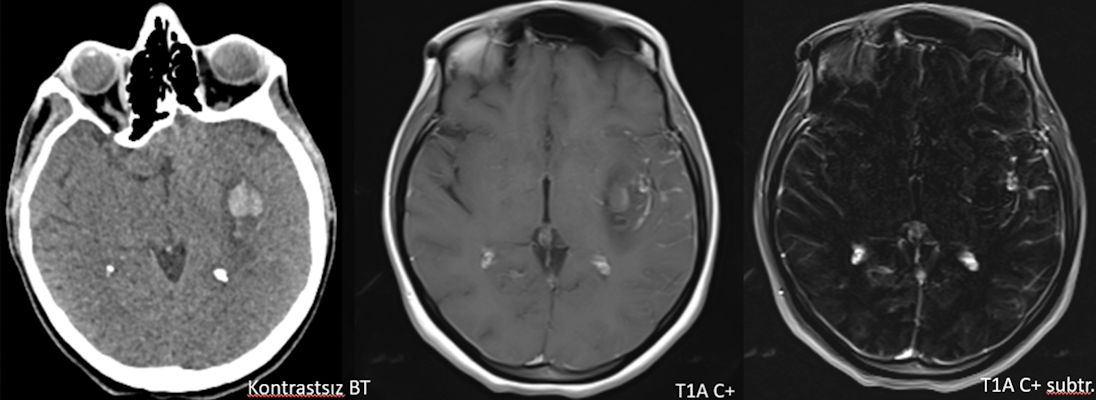

- Aksiyel (A) ve koronal (B) T2A görüntülerde sol insüler bölgede MCA M2 segmenti düzeyinde nodüler düşük sinyalli alanlar (oklar) ve vazojenik ödem ile uyumlu hiperintens alanlar (yeşil oklar) izleniyor.

- Kontrastlı T1A görüntüde (C) ve kontrastlı T1A çıkarma görüntüde (D) medialde bulunan alanda kontrastlanma izlenmezken (ok), lateralde bulunan boyutça daha küçük alanda kontrastlanma izleniyor (ok). Ayrıca anevrizma komşuğunda silvian fissürde leptomeningeal kontrastlanma görülüyor.

- Kontrastsız BT görüntülemede (E) bu düzeyde intraparankimal kanama ile uyumlu hiperdens alan gözleniyor (ok).

- Difüzyon ağırlıklı görüntülemede (F) difüzyon kısıtlanması izlenmiyor.